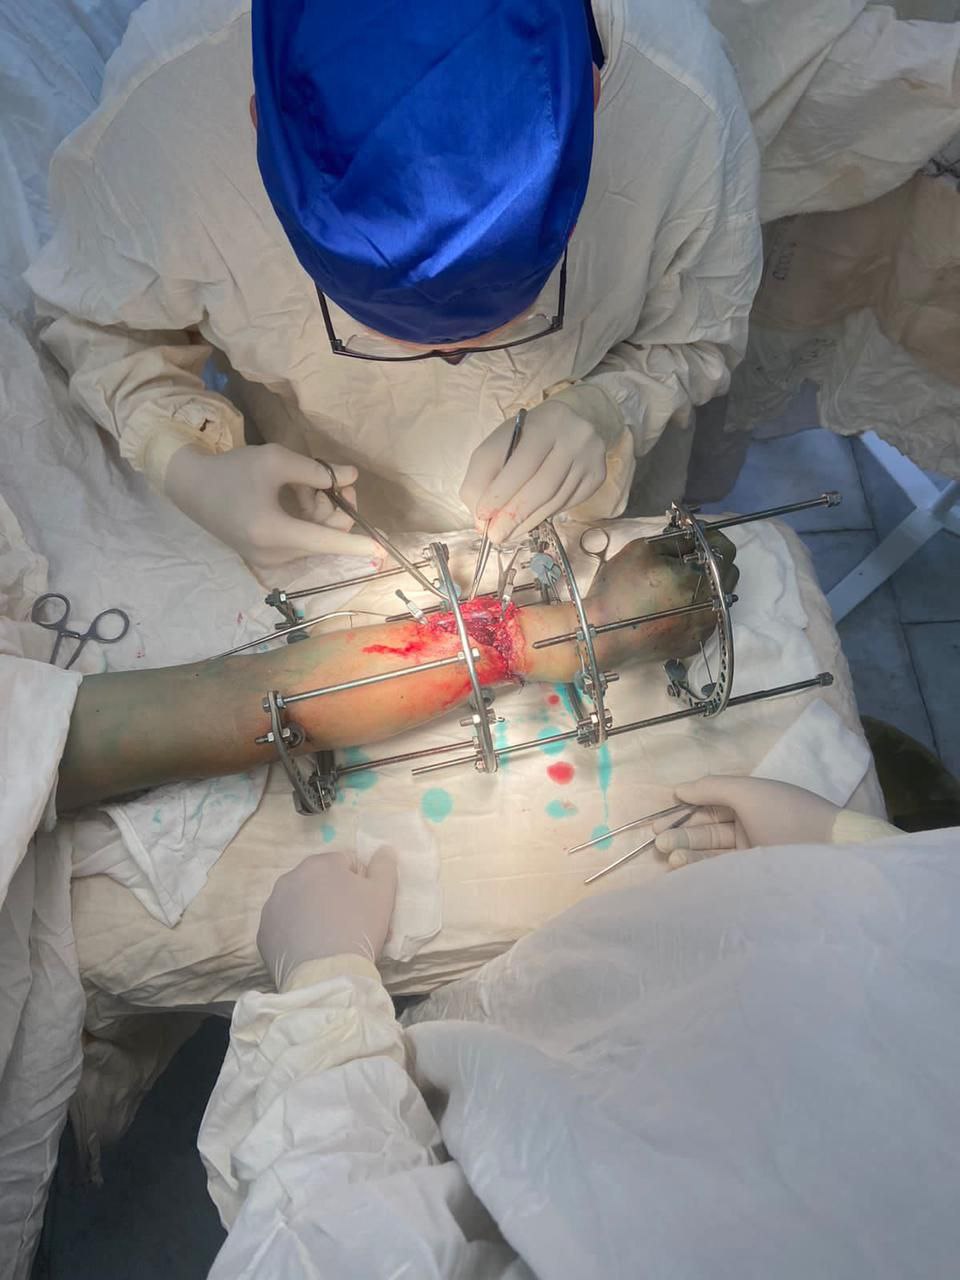

Во время распила досок кисть мужчины попала под циркулярную пилу, и та рассекла обе кости, сухожилия, артерии и вены. Медики совершили чудо.

Во время распила досок кисть мужчины попала под циркулярную пилу, и та рассекла обе кости, сухожилия, артерии и вены. Медики совершили чудо.

Мужчина ремонтировал дом. Он пилил доски циркулярной пилой, и его правая рука соскочила. Пила практически отсекла ее, кисть повисла на сухожилии. Обе кости были разрезаны, так же как вены, артерии, нервы и все остальные сухожилия.

Мужчине наложили жгут, но он все равно потерял много крови. Скорая доставила его в Клинический медико-хирургический центр, где его ждала бригада сосудистых хирургов областной клинической больницы. Травматологи зафиксировали кости с помощью аппарата Илизарова, сшили сосуды и восстановили кровоток.

– И вот спустя две недели пациент выписан домой с аппаратом Илизарова. Через небольшой срок ему предстоит повторная госпитализация и операция по дальнейшему остеосинтезу лучевой и локтевой костей и, конечно же, длительная реабилитация, чтобы постараться восстановить функциональность правой кисти, – рассказал сосудистый хирург Максим Герасименко.

Мужчина ремонтировал дом. Он пилил доски циркулярной пилой, и его правая рука соскочила. Пила практически отсекла ее, кисть повисла на сухожилии. Обе кости были разрезаны, так же как вены, артерии, нервы и все остальные сухожилия.

Мужчине наложили жгут, но он все равно потерял много крови. Скорая доставила его в Клинический медико-хирургический центр, где его ждала бригада сосудистых хирургов областной клинической больницы. Травматологи зафиксировали кости с помощью аппарата Илизарова, сшили сосуды и восстановили кровоток.

– И вот спустя две недели пациент выписан домой с аппаратом Илизарова. Через небольшой срок ему предстоит повторная госпитализация и операция по дальнейшему остеосинтезу лучевой и локтевой костей и, конечно же, длительная реабилитация, чтобы постараться восстановить функциональность правой кисти, – рассказал сосудистый хирург Максим Герасименко.